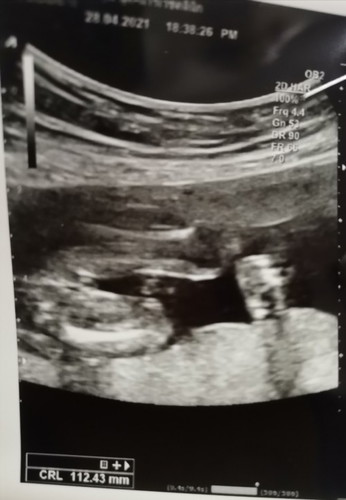

แม่ๆคะสอบถามหน่อยคะ

แบบนี้ลูกสาวหรือลูกชายคะ

น่าจะลูกสาวค่ะ

น่าจะสาวนะคะ